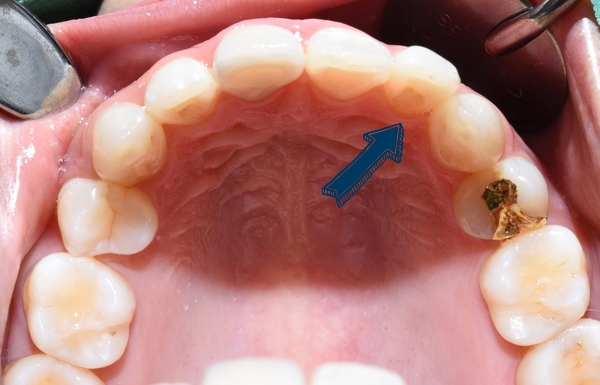

이렇게 말이죠. 위 사진의 환자분의 아래쪽 치아입니다.

다른 치과에서 교정이 끝나고 아래쪽만 유지장치를 붙이고 위쪽은 안붙이셨나봐요.

그래서 이 환자분의 경우

보이지 않는 방식으로 교정을 원하셨기 때문에

보이지 않게 설측에 붙이는 티끌교정으로 진행하였습니다.

치아안쪽에 장치를 부착하기 때문에 겉에서는 보이지 않습니다.